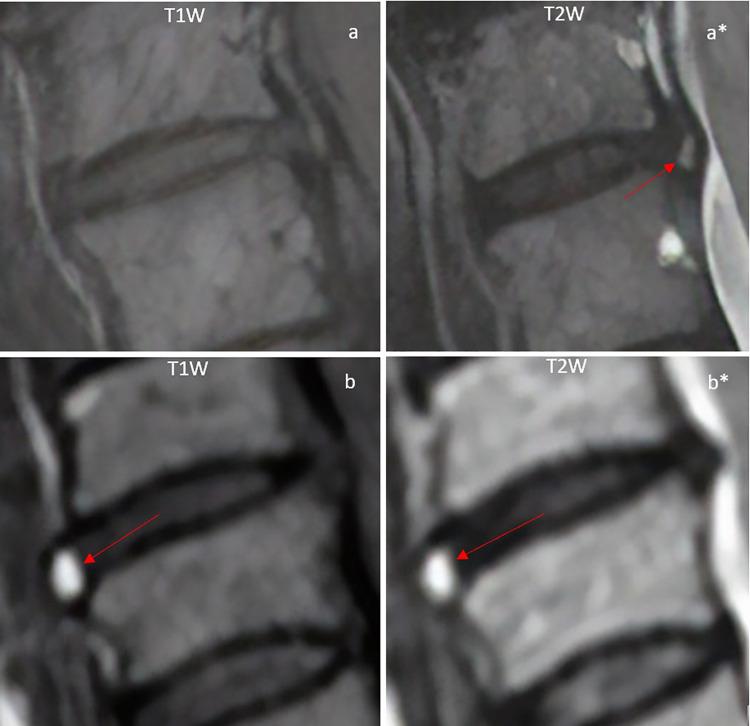

A retrospective cohort study of ACDF patients surgically treated at a single center from 2008 to 2015. Based on preoperative MRI, HIZ subtypes were identified as either traditional T2-hyperintense, T1-hypointense ("single-HIZs"), or combined T1- and T2-hyperintense ("dual-HIZs"), and their level-specific prevalence was assessed. Preoperative symptoms, patient-reported outcomes, and disc degeneration pathology were assessed in relation to HIZs and HIZ subtypes.

对2008年至2015年在单一中心接受手术治疗的ACDF患者进行回顾性队列研究。根据术前MRI,HIZ亚型被确定为传统的T2高信号、T1低信号(“单一HIZs”)或T1和T2高信号合并(“双重HIZs”),并评估其节段特异性患病率。术前症状、患者报告的结果以及椎间盘退变病理与HIZs和HIZ亚型相关进行评估。